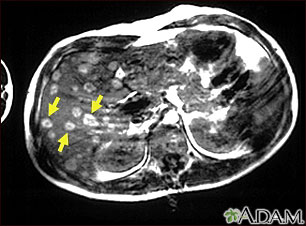

This upper abdominal MRI scan shows multiple tumors in the liver which have spread (metastasized) from a malignant melanoma in an arm or leg. Note the light circular areas throughout the liver (seen mostly on the left side of the screen).